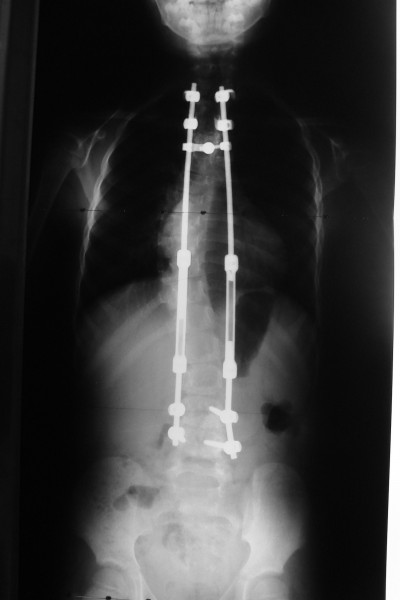

Korse tedavisine yanıt alınamadığı durumlarda cerrahi tedaviye başvurulur. Cerrahi tedavi büyümesi devam eden ve büyümesi tamamlanmış hastalarda farklılık ihtiva eder. Büyümesi tamamlanmamış çocuklarda büyüme dostu implantlar (uzayan rod, magnetik rod, bantlama yöntemi vs.) kullanılır. Büyümesi tamamlanmış çocuklarda ise en sık yapılan cerrahi işlem sırttan vida ve çubuklar kullanılarak enstrümentasyon ve kemik greftiyle yapılan füzyondur. Modern enstrüman sistemleri ile eğriliği %80 oranında düzeltmek mümkündür.